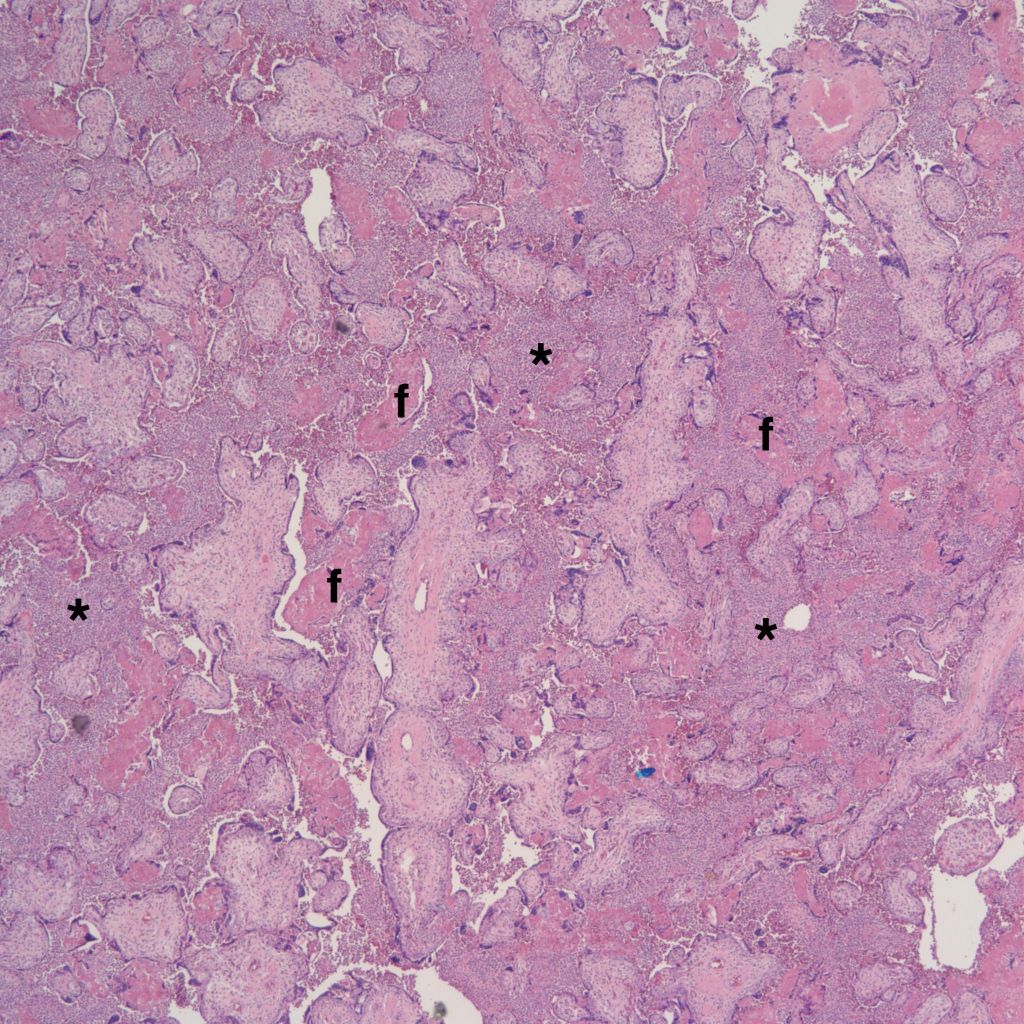

High Grade (massive) CHIV

Low Grade CHIV (5-50% of the intervillous space occupied by monocytes)

There is a focus of intervillous fibrinoid with no definite cytotrophoblast that is not re-covered with syncytium suggestive of recent syncytial injury (F). (10x, H&E)

CHIV with prominent perivillous fibrinoid deposition

CHIV associated with Villitis of Uknown Etiology (VUE)